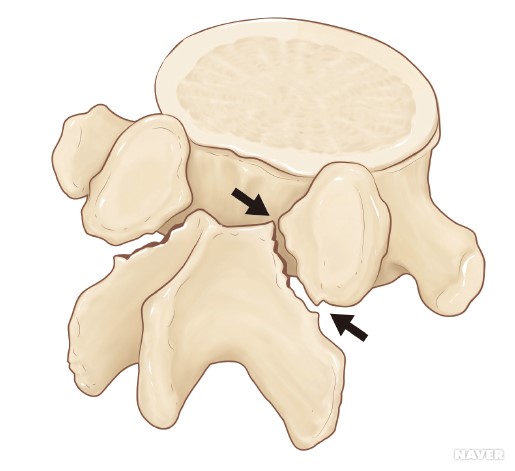

●척추분리증 [spondylolysis]

​척추의 후방에는

상관절 돌기와 하관절 돌기가 있어,

각각 위의 척추 및 아래의 척추와 관절을 이루는데,

상관절 돌기와 하관절 돌기 사이에 있는 관절 간에

좁아진 부위에 결손이 발생한 상태를 말하며

협부에 스트레스성 골절이 발생하는 경우가 가장 많다.

5번 요추에 가장 흔하게 나타난다.